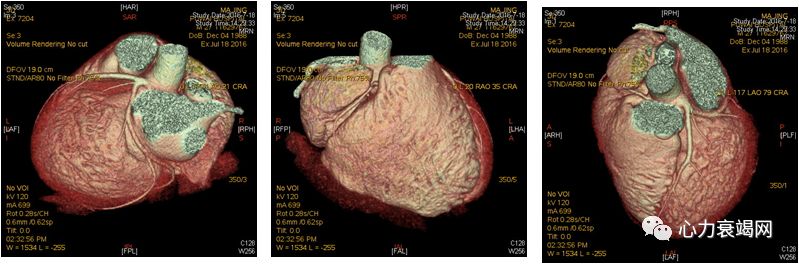

冠状动脉CT

冠状动脉平扫未见钙化,无明确狭窄,左室大